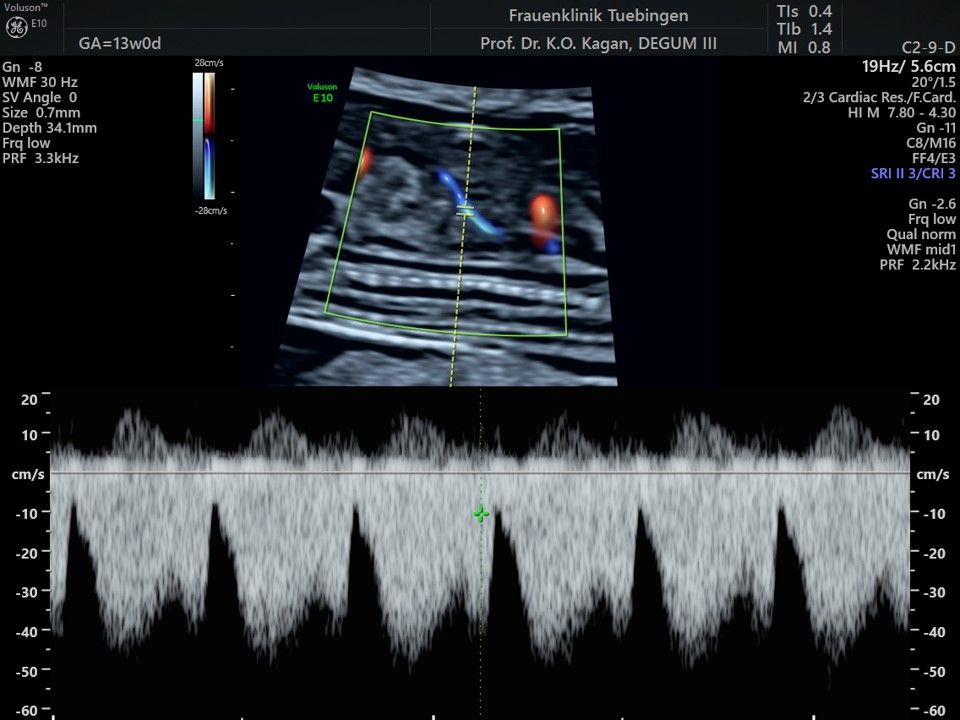

Das Ergebnis der Ultraschalluntersuchung ist wegweisend. Dabei wird der Fet vermessen, die Organe werden untersucht und die sonographischen Marker zur Risikoberechnung für Chromosomenstörungen werden beurteilt. Das sind: die Nackentransparenzdicke, Nasenbein sowie der Blutfluss in der rechten Herzhälfte und im Ductus venosus, einem Gefäß in der Leber des Feten.

Mithilfe des Ersttrimester-Screenings kann das persönliche Risiko einer Präeklampsie bestimmt werden. Dazu wird die Vorgeschichte der Schwangeren, der aktuelle Blutdruck, das Ergebnis der Ultraschalluntersuchung (Widerstand in den Gebärmutter-nahen Gefäßen) und der Blutabnahme bei Ihnen (PAPP-A) kombiniert. Sollte das Risiko über 1:100 sein, empfehlen wir die tägliche Einnahme von Aspirin 150mg bis zu 35.SSW und eine gezielte Überwachung der weiteren Schwangerschaft.